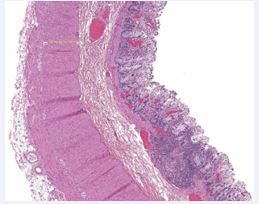

Figure 3 Hematoxylin and eosin staining of control group tissue. The section demonstrates normal-appearing muscular thickness of both the inner and outer layers of the muscularis propria, with preserved overall histological architecture.

Histopathological examination revealed significant hypertrophy of both the inner and outer muscular layers of the muscularis propria, thickened nerve fibers, and increased lamina propria width in all patients compared to the control group (Table 2, Figures 2A/B, Figure 3, Figure 4, Figure 5A/B and Figure 6A/B). Notably, the increased thickness of the lamina propria was primarily attributed to fibrosis (Figures 4A and 4B). The distal portion (rectum) of the specimens exhibited more prominent fibrosis compared to the proximal portion (sigmoid), although no morphometric analysis was performed for this aspect.